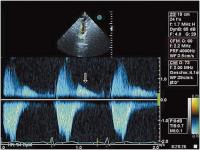

Abbildung 1: Endokarditische Vegetation (Veg) an der akoronaren Taschenklappe (Ao = Aorta ascendens; LA = linker Vorhof)